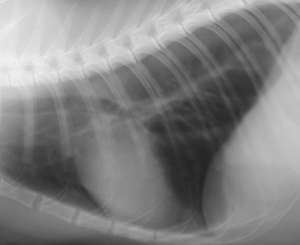

次にイメージングプレートのCRレントゲンとFPDによるDRレントゲンの画像比較をしてみたいと思います。下の写真はそれぞれ同じ猫の正常な胸部レントゲン写真です。違いがお分かりになるでしょうか?

上がCRで下写真が次世代のDRによるものです。

DRレントゲンの画像の方がくっきり明瞭に見える一方、CRではやや曖昧な印象を受けると思います。